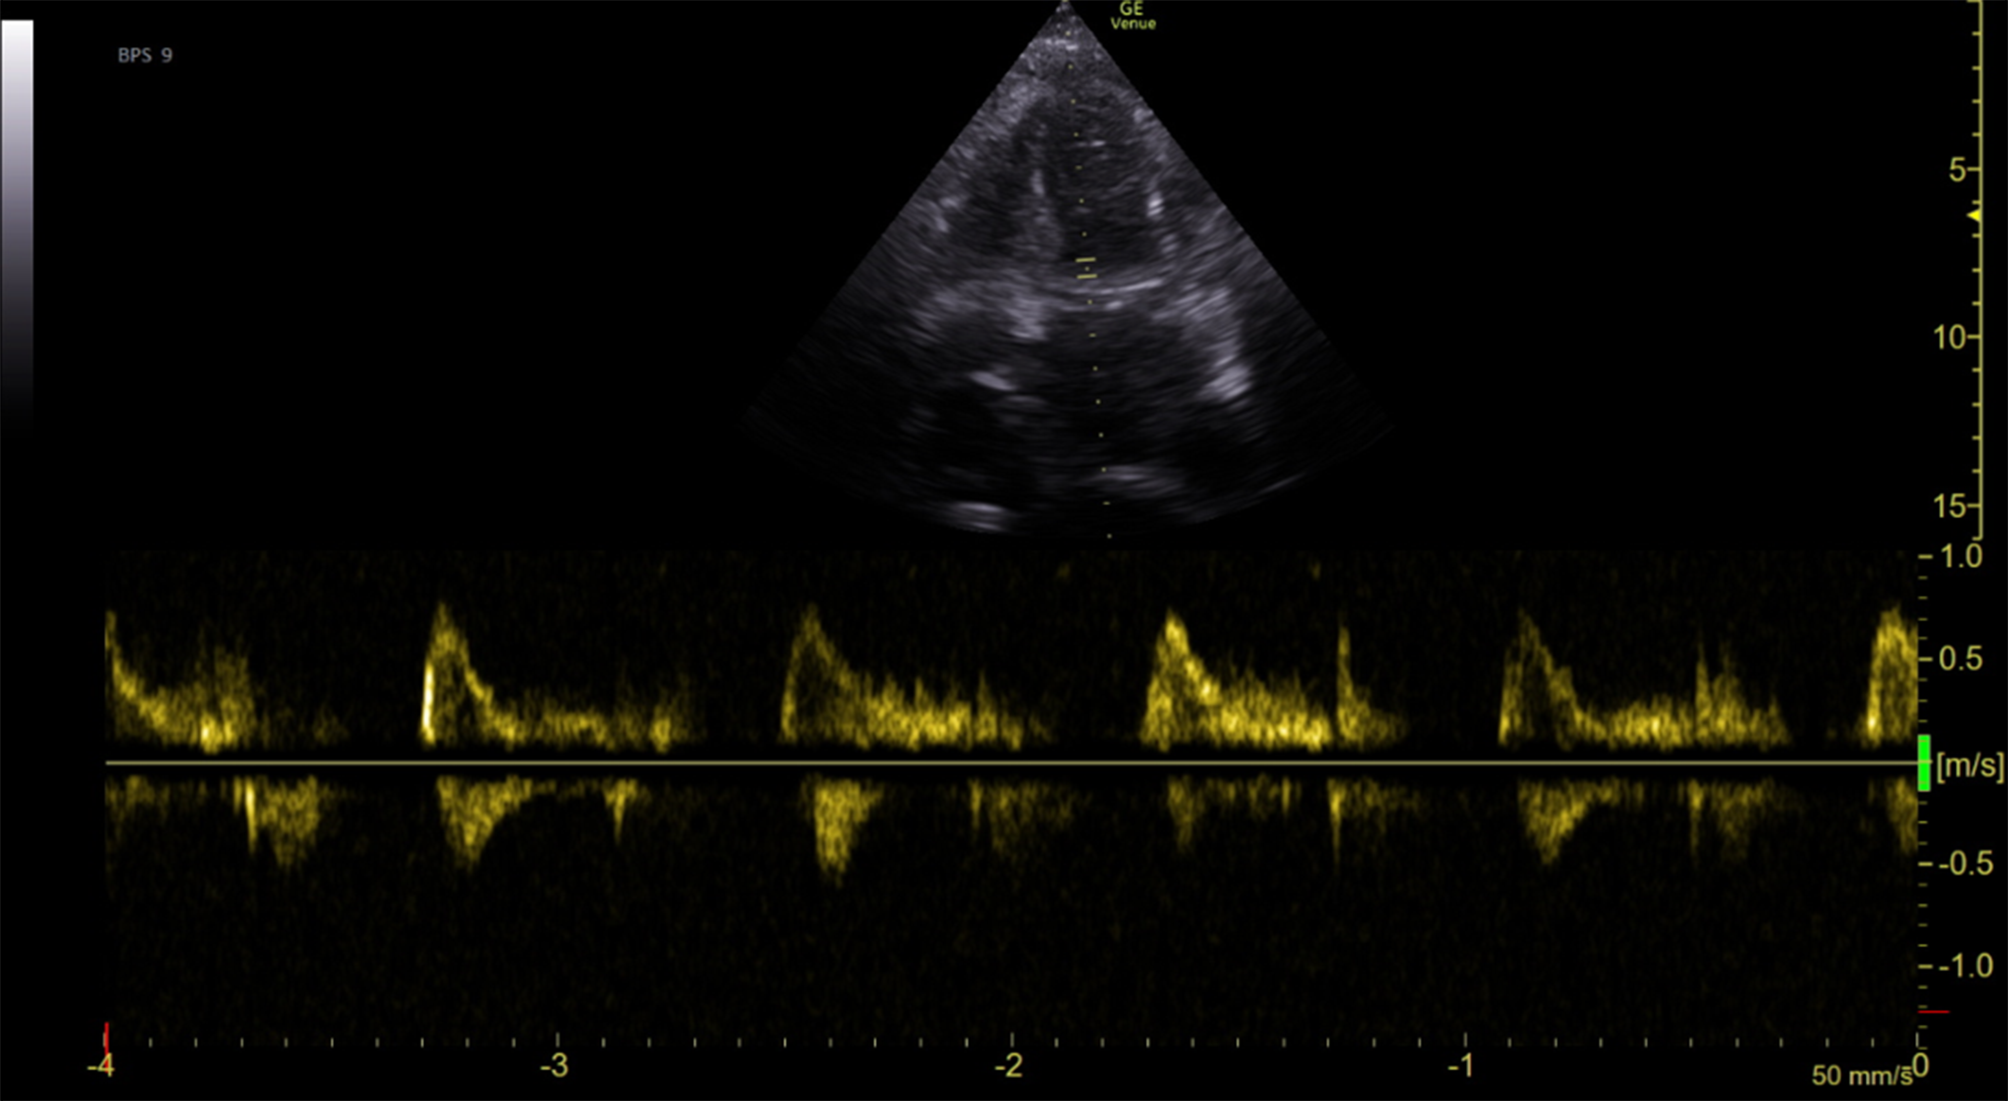

Nevertheless, the patientʼs overall health started to deteriorate. Despite diuretic and antibiotic treatment, the clinical condition gradually worsened and she complained about vertigo and dyspnea. Arterial blood gas analysis performed 2 weeks after admission due to hyperventilation indicated severe lactic acidosis (lactate 16 mmol/L, pH 7.2). At admission to the cardiac care unit (CCU), transthoracic echocardiography showed a hypertrophic left ventricle with hyperdynamic systolic function and restrictive filling pattern (Fig. 1) compatible with the diagnosis of heart failure with preserved ejection fraction due to infiltrative cardiomyopathy. Despite all measures taken lactic acidosis escalated further and 6 h after CCU admission the patient had a cardiac arrest in the context of pulseless electrical activity and passed away.

Fig. 1

Transthoracic echocardiography showing a hypertrophic left ventricle with hyperdynamic systolic function and restrictive filling pattern